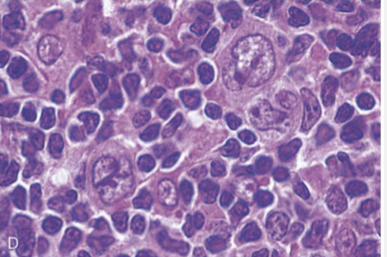

Burkitt lymphoma

Highly aggressive B-cell neoplasm characterized by the overexpression of the Myc gene on Chromosome 8

Translocation is the IgH heavy chain locus t(8;14)

Starry Sky appearance due to evenly interspersed macrophages with apoptotic debris in cytoplasm

Intermediate to small cells with noncleaved nuclei, coarse chromatin, small multiple nucleoli & very high mitotic index